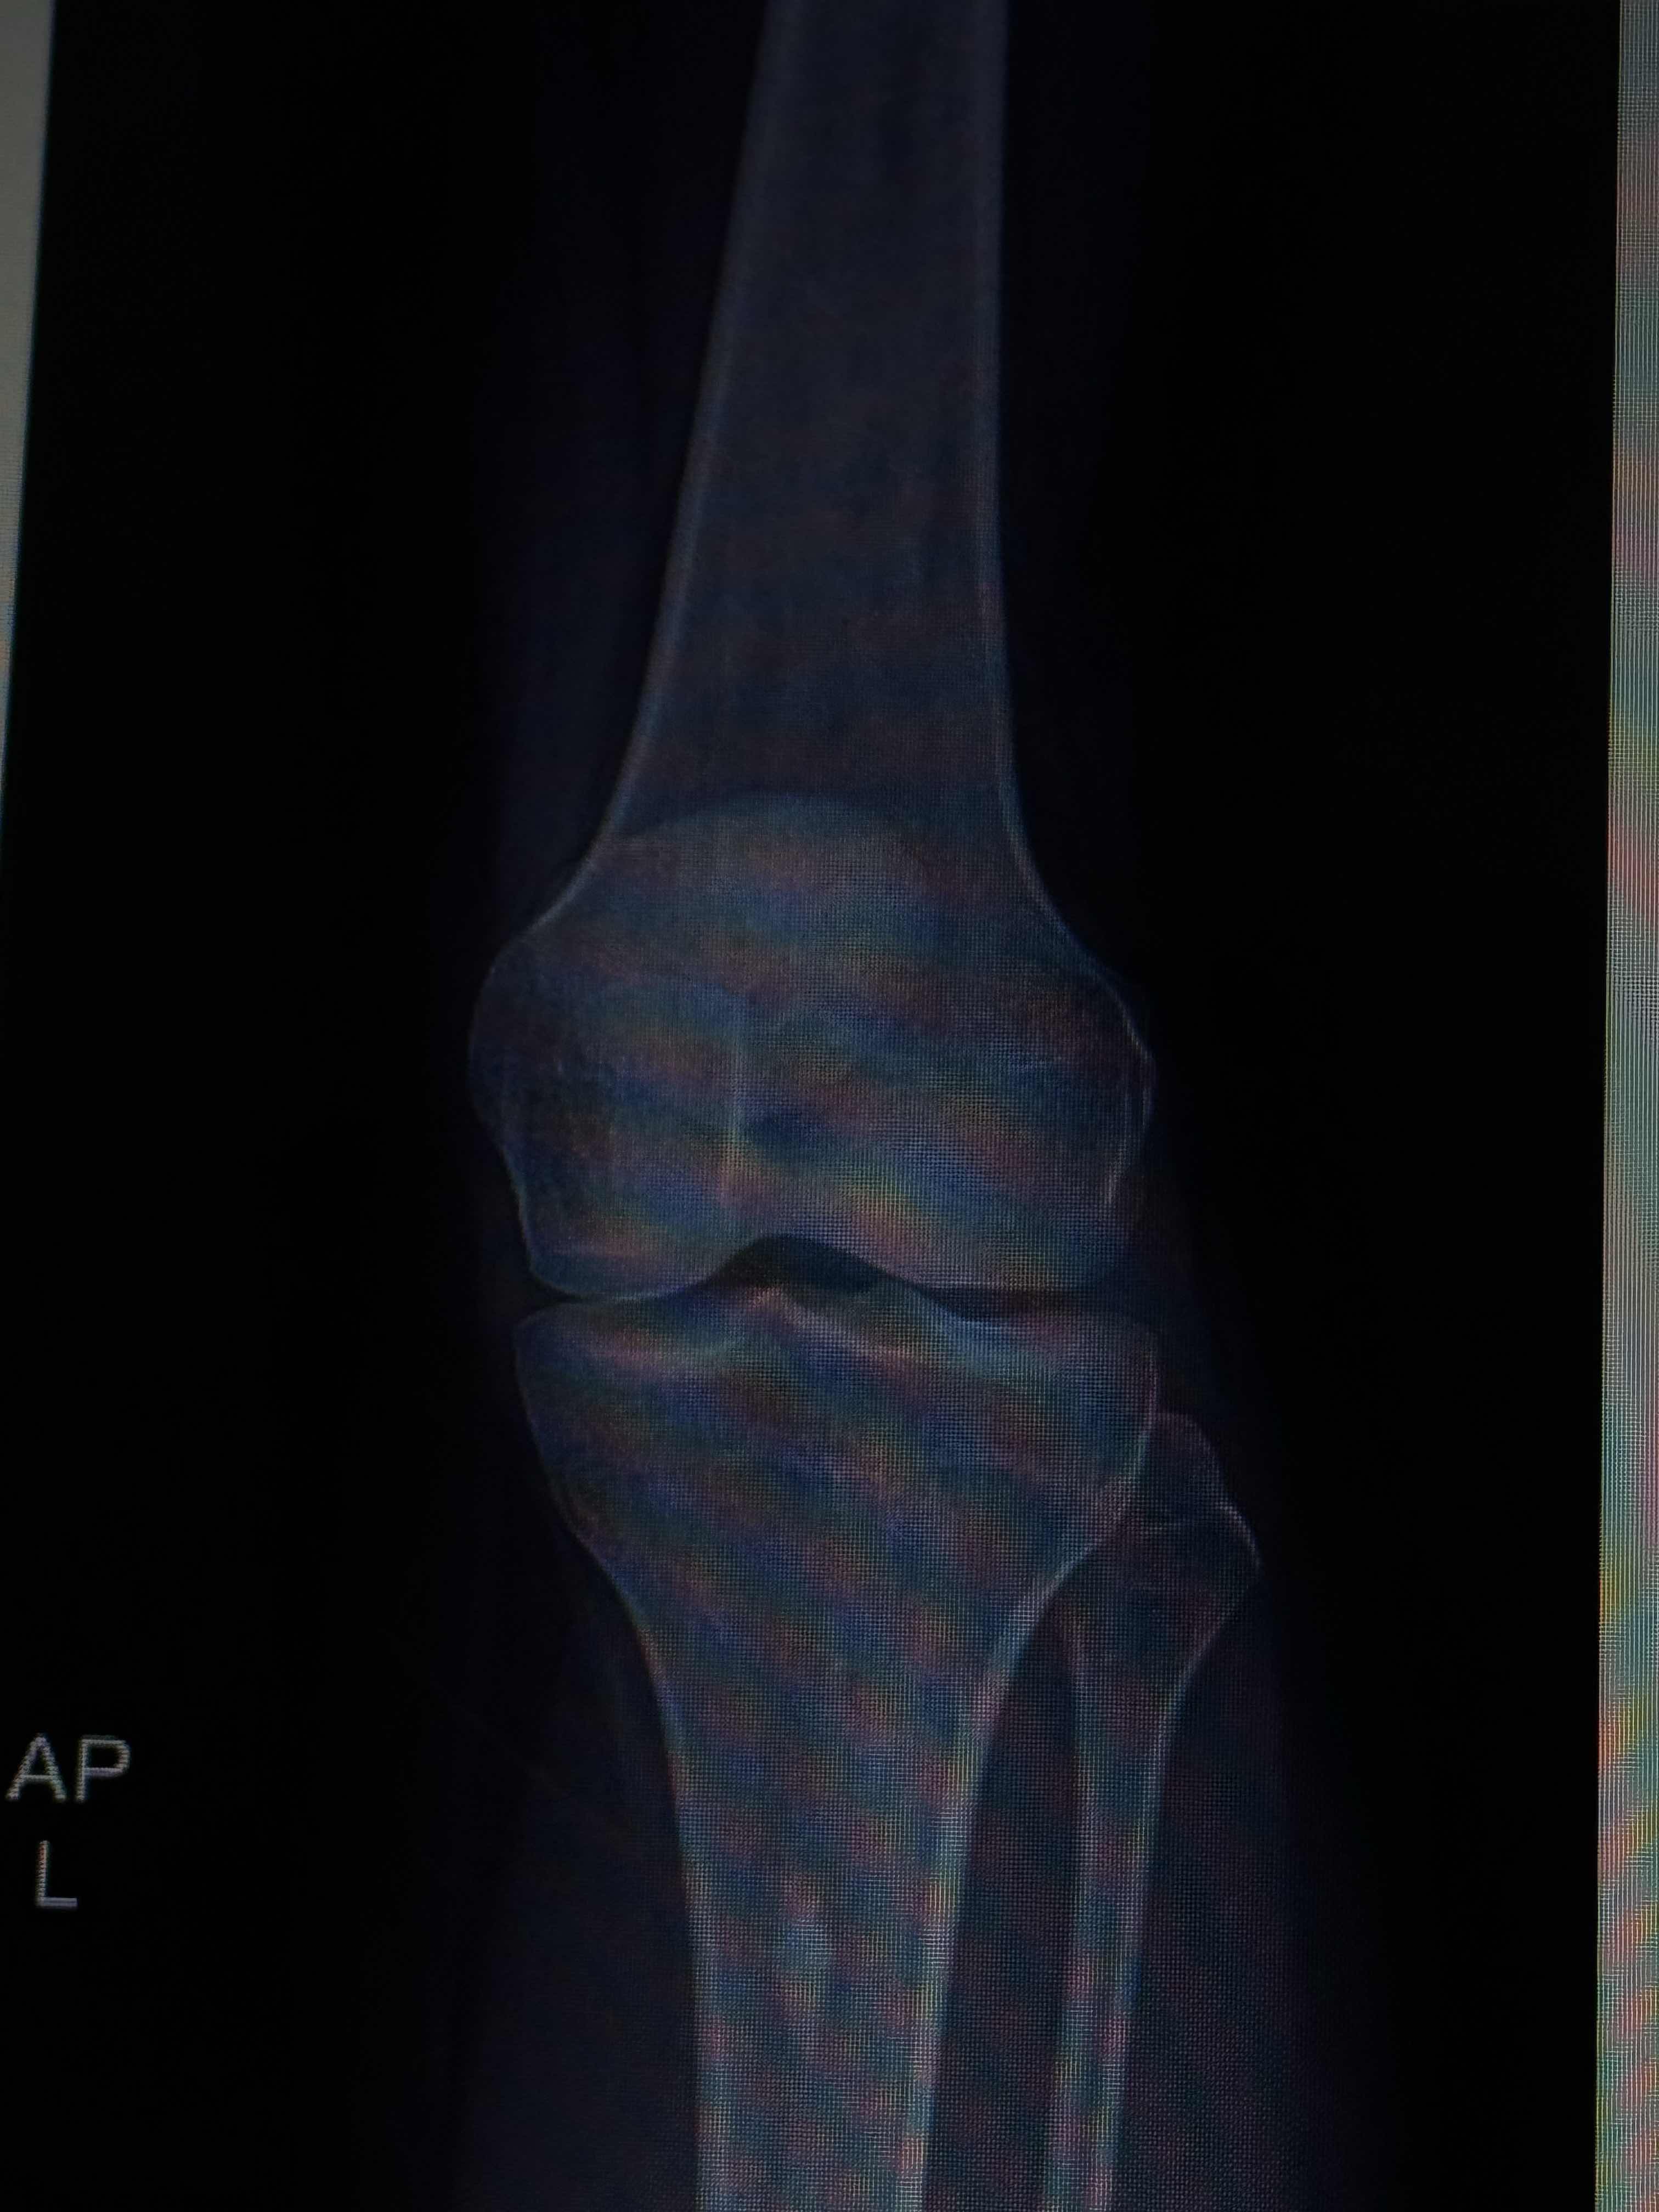

عندي مشكله بركبتي اليسار اذا كنت جالسه وثانيتها وقت طويل بدون حركه بالذات على المكيف تصير توجعني ومقدر امشي بكل سلاسه عليها عكس اذا كنت مادتها عادي لو ساعات

B0A53CFA-4E52-455E-BE74-34B416818F1B